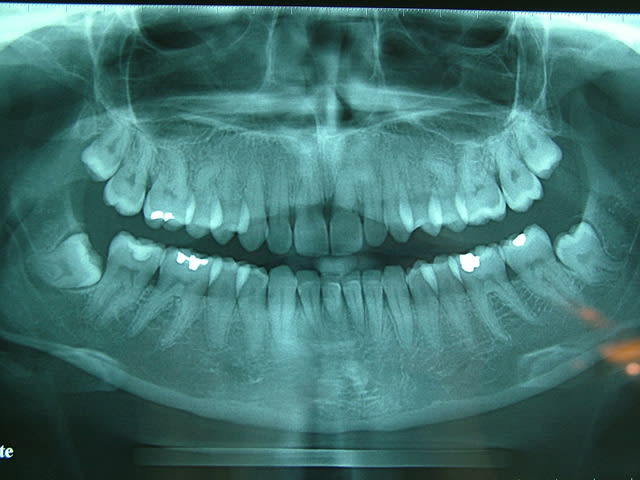

Comme promis la Rx pano,je la revois dans 15 jours pour un détartrage.J'ai expliqué à la patiente ce qu'il en était,je vais essayer de temporiser un peu vu qu'elle n'en souffre pas....

pas vraiment de problèmes paro...mais l'ortho à laissé des "traces"...:-(

sur la première radio, il me semble aussi que la 11 est touchée (en distal) et de toutes façons la racine est elle aussi bien rhizalysée...

pour moi, c'est bien parti pour être un cas avec 2 implants 11 et 21 en EII et MCI...

+1 pour un bilan radio approfondit...même déjà simplement une pano...